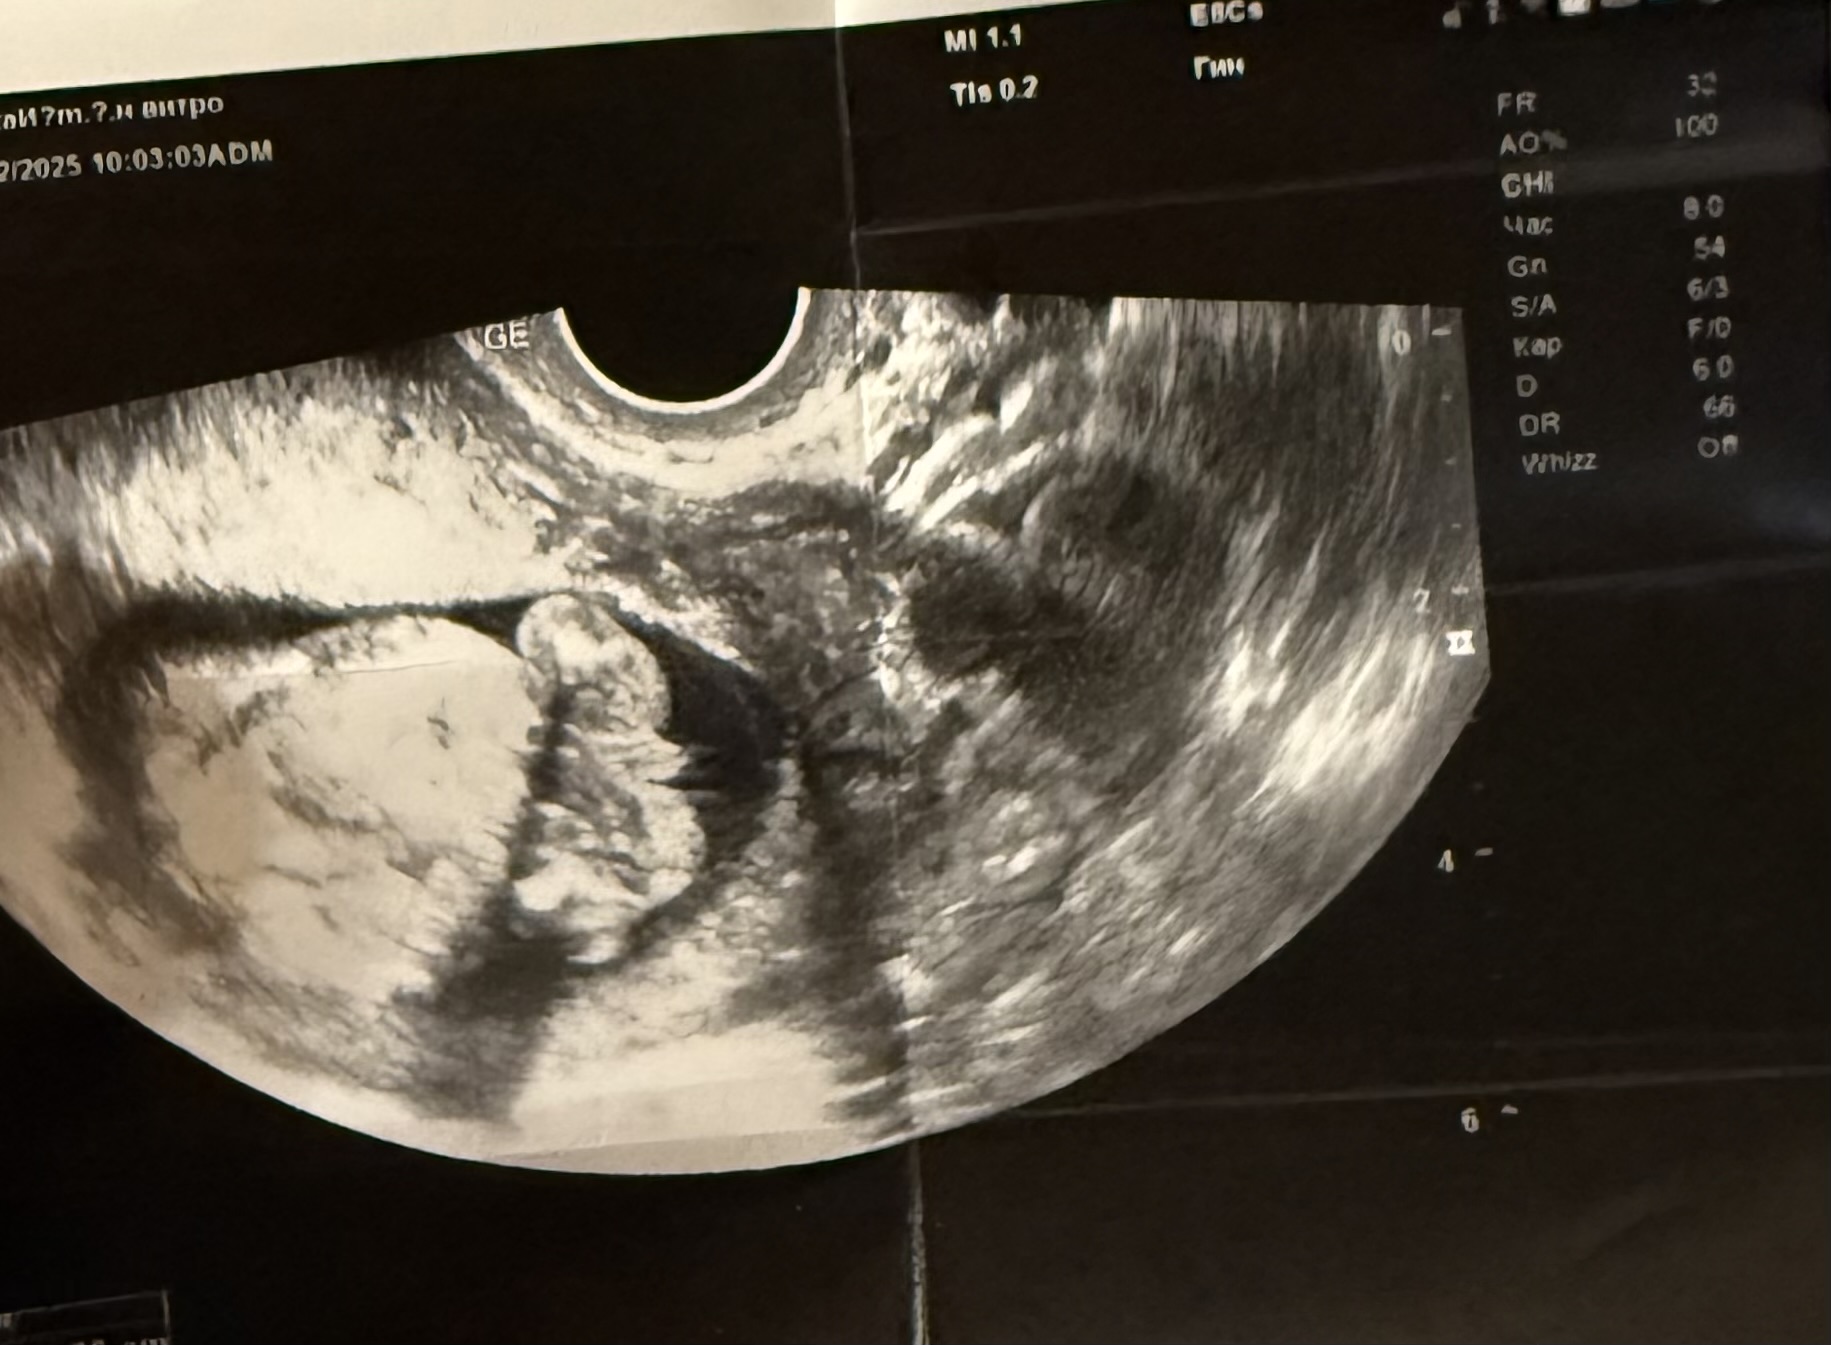

Кто в теме, подскажите пжста, веду беременность платно, на первом скрининге за пол я не спрашивала, так как понимала что срок маленький совсем. На 11 неделе делали. Далее перед отпуском решила сходить сделать узи платно, подсмотреть так сказать за малышом)) Было 14 - почти 15 недель. Я шла просто подсмотреть! А узист закончив первые важные замеры, спросила а не говорили ли мне уже пол? Я ответила что нет, маленький ведь срок. На что она мне сказала ну тут уже все очень даже видно, мальчик у вас будет! Заявила на все 100% и все оставшееся время пока мы там все рассматривали , ручки ножки, она раз 10 сказала что пистолетик видно 😂 Прям уверила . Но мне, честно, тоже показалось сразу это самое, как только началось узи. Фото приложу. И вот вернулась я с отпуск, думаю схожу еще раз , а то второй скрининг только 12 марта. И что вы думаете? В этот раз она молчала на счет пистолетика про который твердила в первый раз 🙈🫠 17 недель и 3 дня по последний мес 🩸 и по малышу написала 16 недель 9 дней. Как в аптеке 😅 Сказала что-то сегодня не видно ничего. Короче малость я расстроилась конечно.. когда тебя так сильно уверяли, а сегодня вот такое) Еще и фотку распечатала пистолетика, сказала мужу показать) эхх Все фото это 14-15 недель